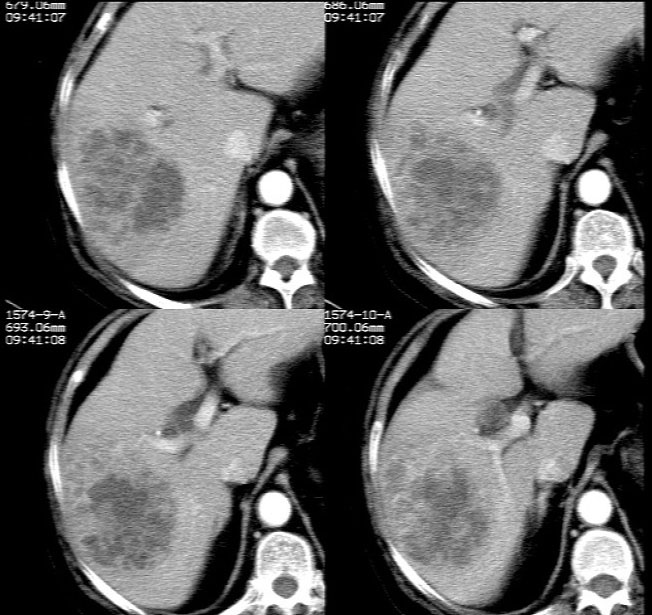

ct增强扫描示: 动脉期肝右后叶团状低密度边缘明显不均性强化,内呈不规则峰窝状低密度(无强化区),不规则分隔亦见明显强化;三期扫描像均见,病灶有明显占位征,周围血管、胆管推挤外移,病灶与正常肝组织分界不清,延迟期病灶周围见雾状略低密度(较肝左叶)。

肝右后叶团状低密度占位性病变,结合临床提示: 1、肝脓肿? 2、不排除肝ca可能。建议afp检查。

平扫示肝右后叶见团状低密度灶,边界欠清,密度略不均匀,ct值28-32hu,肝内胆管无扩张。ct增强扫描动脉期肝右后叶团状低密度边缘明显不均性强化,内见多发斑片状无强化液化区,呈不规则峰窝状。

考虑肝脓肿早期(蜂窝组织炎阶段)。

病灶边缘及其内部分隔呈持续强化,考虑肝脓肿